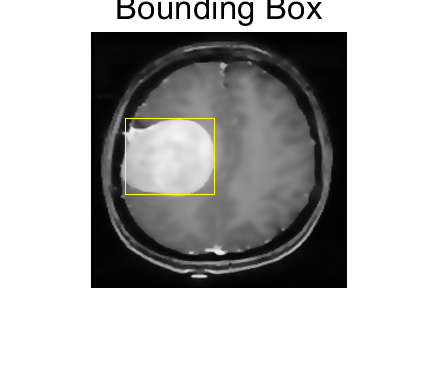

大脑肿瘤(如胶质瘤、脑膜瘤)的早期精准识别是临床诊断与治疗方案制定的核心前提,而磁共振成像(MRI)凭借高软组织分辨率、无辐射损伤的优势,成为大脑肿瘤临床检测的首选影像学手段。然而,原始大脑 MRI 图像常存在噪声干扰(如设备电子噪声、生理运动伪影)、组织边界模糊(肿瘤与正常脑组织灰度差异小)、伪影叠加(如磁化率伪影、血管搏动伪影)三大问题,导致传统视觉诊断或简单阈值分割方法的识别精度低、漏诊 / 误诊率高。

各向异性扩散滤波器(Anisotropic Diffusion Filter, ADF)作为一种自适应图像增强技术,可在保留图像边缘细节的同时抑制噪声—— 其核心优势在于:根据图像局部梯度信息动态调整扩散强度,在平坦区域(如正常脑组织内部)增强扩散以降噪,在边缘区域(如肿瘤与正常组织交界)减弱扩散以保留边界特征。将 ADF 与深度学习识别模型结合,构建 “预处理 - 特征提取 - 肿瘤定位 - 分类” 的完整技术流程,可有效提升大脑 MRI 图像中肿瘤的识别精度与临床实用性,为神经外科医生提供可靠的辅助诊断工具。